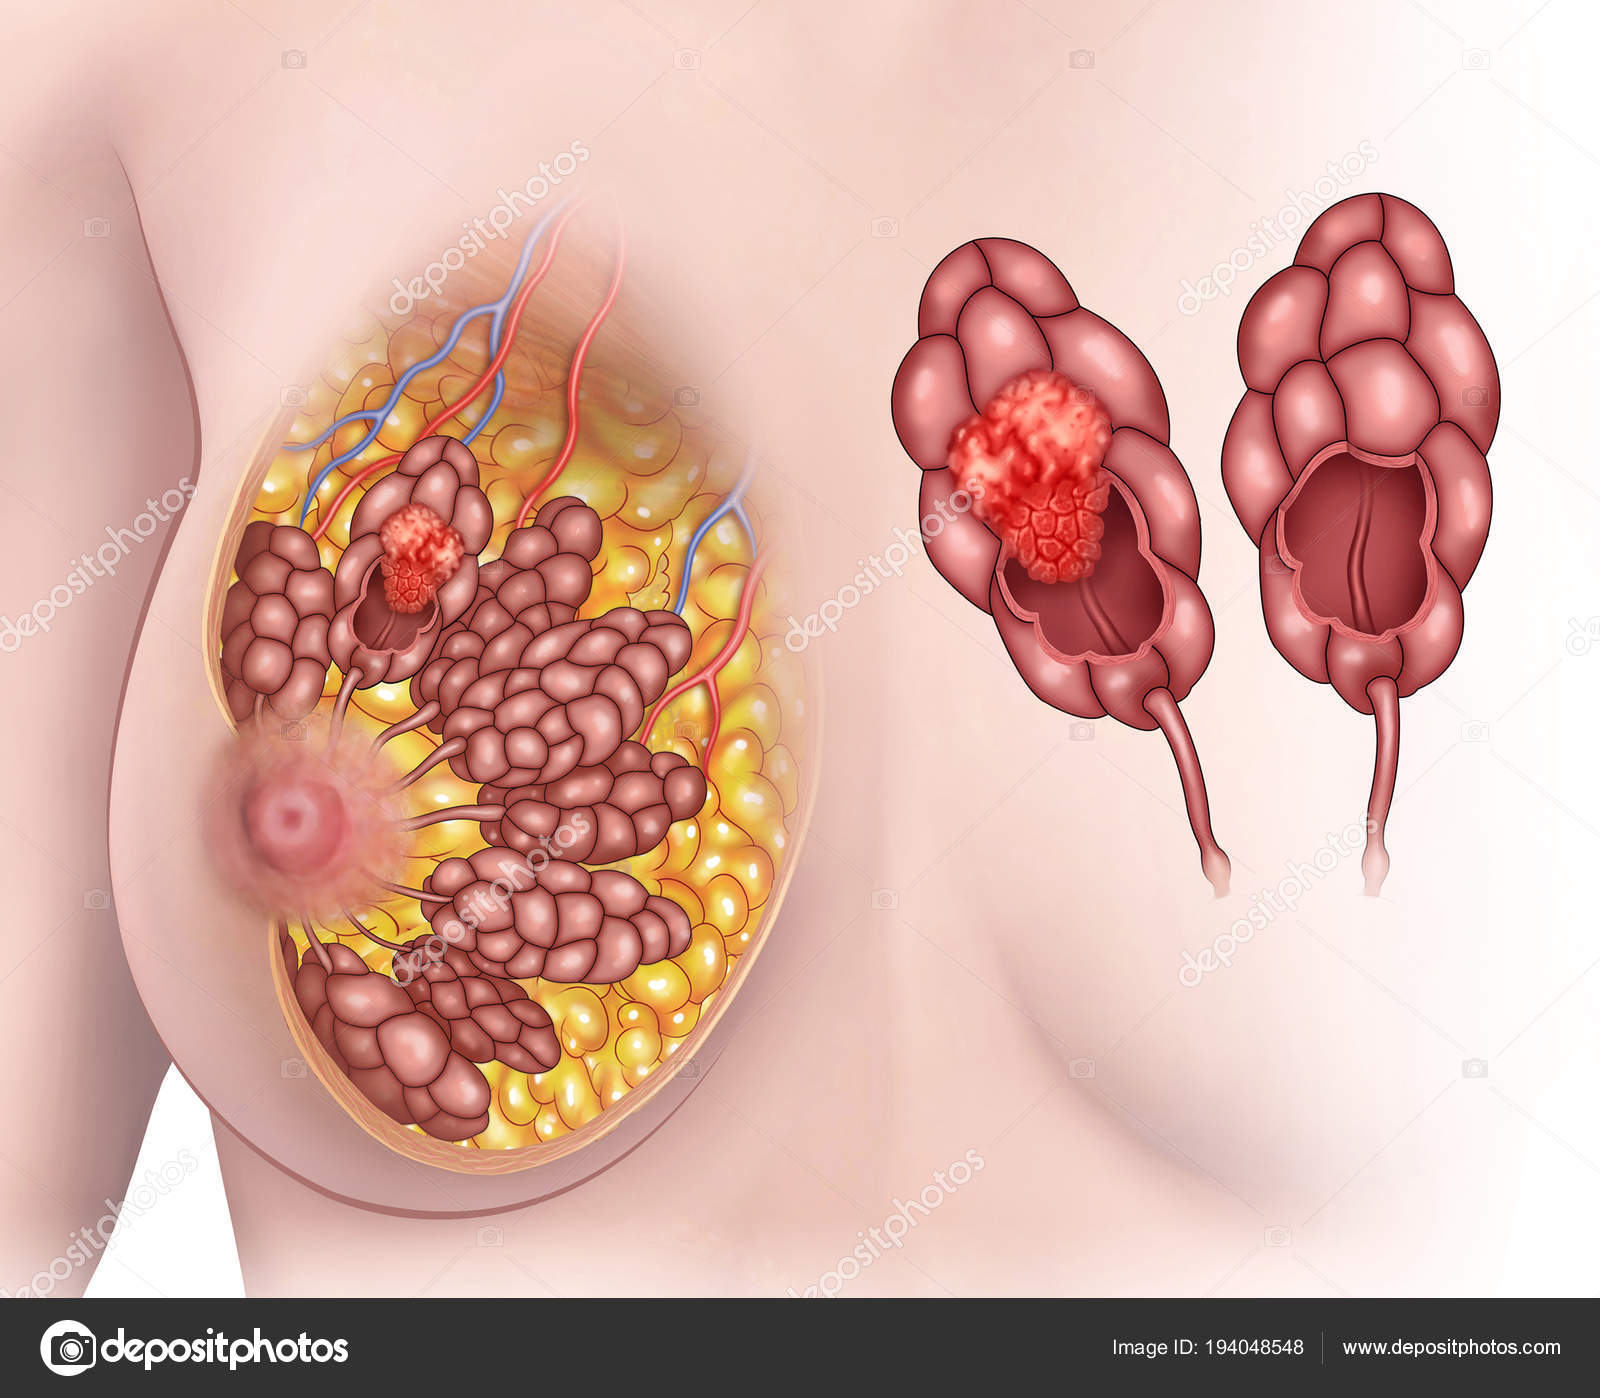

Фото раковой шишки на теле

Раковые шишки могут возникать не только на лице, но и на других частях тела. На фотографиях вы можете увидеть примеры раковых шишек на шее, руках, ногах и туловище. Обратите внимание на различные формы и размеры раковых шишек, а также на их внешний вид.